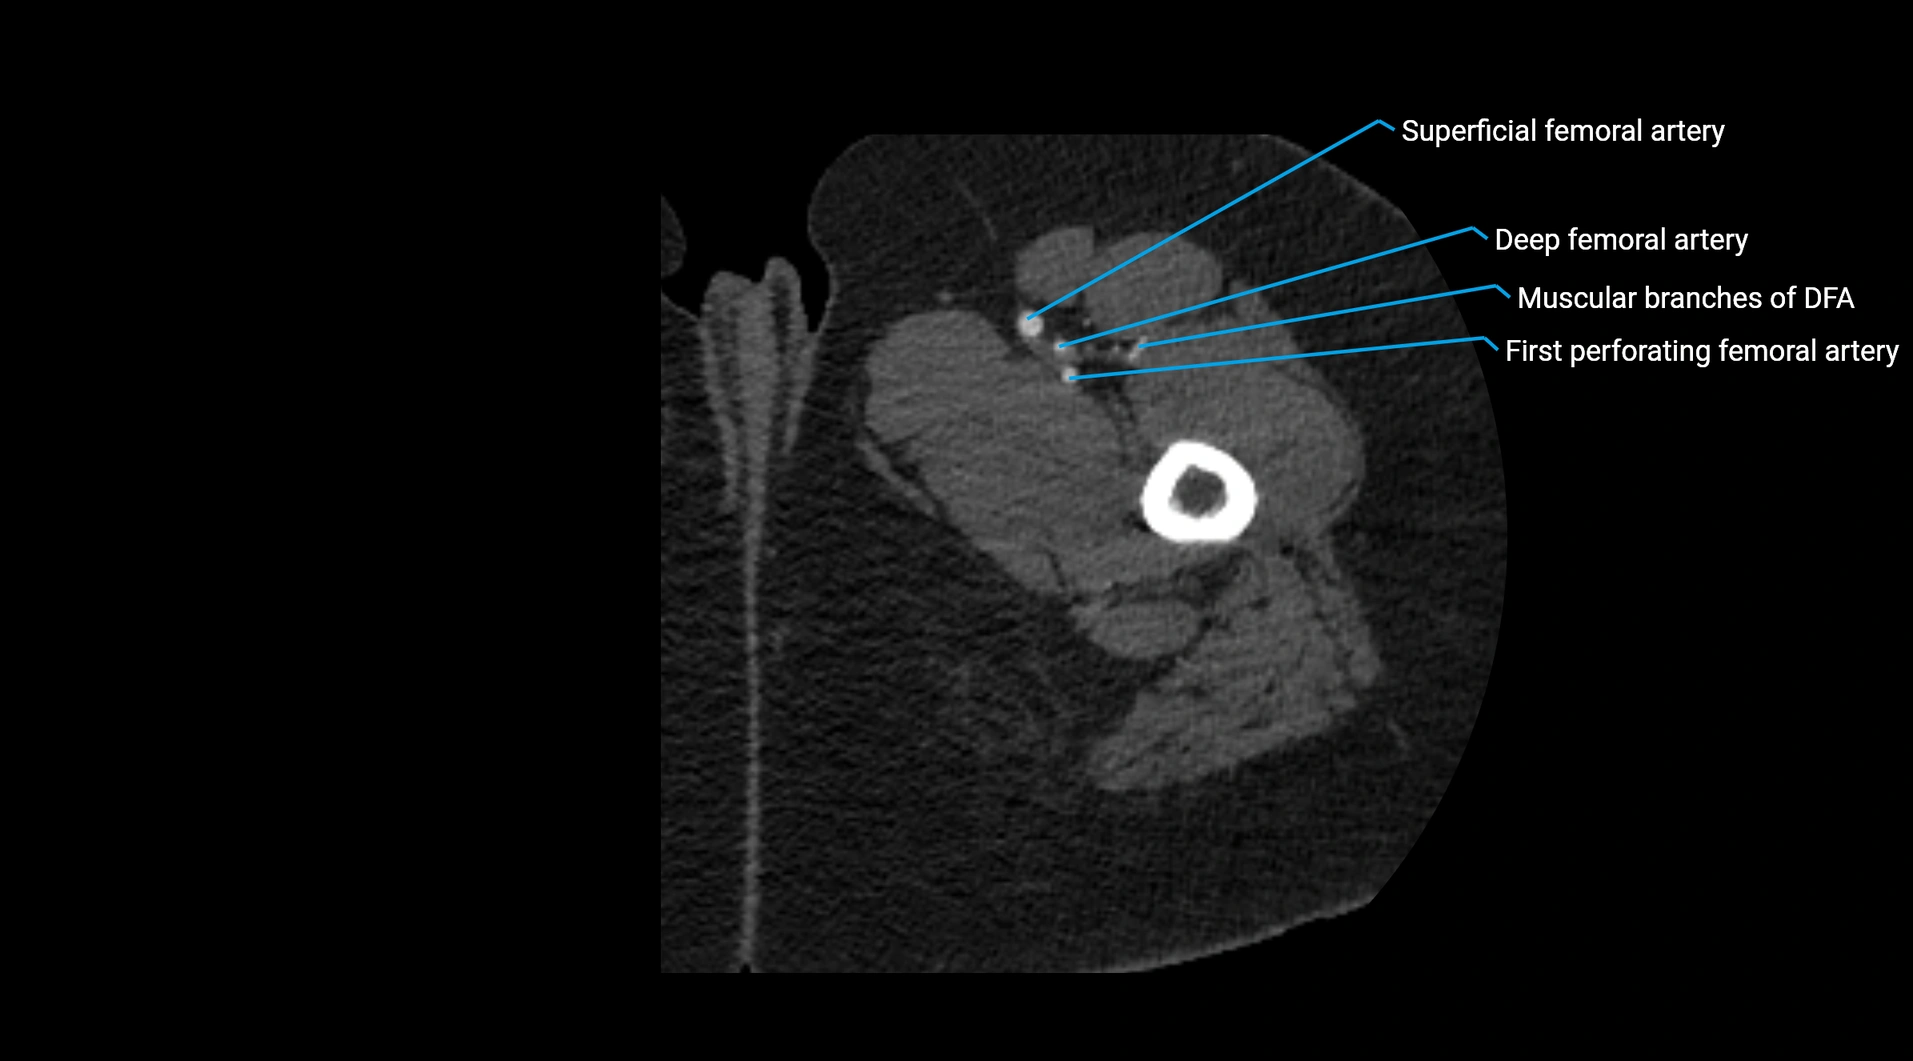

Contrast-enhanced CT (CTA):

• Gold standard for abdominal aortic imaging

• Provides excellent detail of lumen, wall, aneurysm, thrombus, and branch vessels

• Multiplanar and 3D reconstructions help in aneurysm measurement, stent graft planning, and dissection evaluation

• Detects acute rupture, traumatic injury, or occlusion with high sensitivity